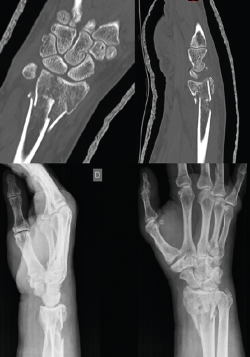

Figura 2. Control posquirúrgico (6 semanas).

Se realiza radiografía simple y tomografía axial computarizada (TAC) (Figura 1). Se llevó a cabo la osteosíntesis con una placa volar Acu-Loc 2® distal ancha larga de Acumed y aporte de hueso de banco liofilizado en el foco metafisario. Se consiguió una reducción correcta (Figura 2). La herida evolucionó sin incidencias y se mantuvo al paciente 3 semanas inmovilizado con férula en U bloqueando la pronosupinación (sugar tongue). Posteriormente, inició una rehabilitación progresiva, con uso de ortesis rígida de descarga y controles clínicos y radiológicos cada 4-5 semanas.